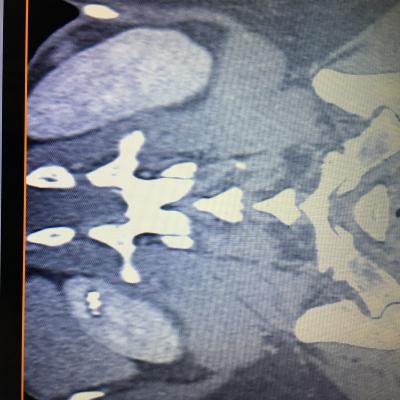

Здравствуйте,помогите, пожалуйста, с расшифровкой кт почек с контрастом. Насколько я поняла, в левой почке маленький камешек. А что за образование в правой почке? Киста с кальцинированной стенкой или камень? Спасибо за ответ!

Здравствуйте! На последнем снимке - больше данных за конкремент. Но при описании снимков должны определяться плотность образования, и нет изображения ни одного фрагмента ни одного из мочеточников. И самих снимков обычно бывает больше. Недостаточно данных для заключения.